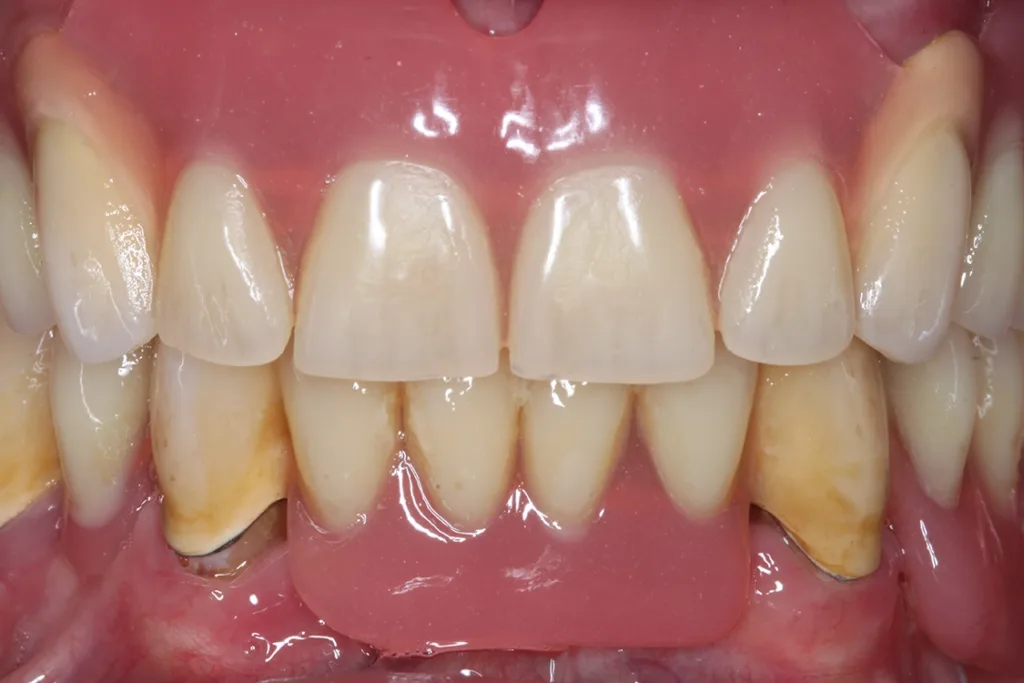

Abb. 3 a–e: Klinische Dokumentation eines 63-jahrigen männlichen Patienten (geb. 05.09.1961). Die Fotodokumentation erfolgte erst am Tag der AIT und nicht im Rahmen der klinischen und radiologischen und 47 wurden vor der AIT entfernt. An den Zahnen 13 und 23 war neben der peniblen subgingivalen Instrumentierung die Applikation von Straumann® Emdogain® (Straumann Group, Basel, Schweiz) vorgesehen.Walter

Abb. 3 a–e: Klinische Dokumentation eines 63-jahrigen männlichen Patienten (geb. 05.09.1961). Die Fotodokumentation erfolgte erst am Tag der AIT und nicht im Rahmen der klinischen und radiologischen und 47 wurden vor der AIT entfernt. An den Zahnen 13 und 23 war neben der peniblen subgingivalen Instrumentierung die Applikation von Straumann® Emdogain® (Straumann Group, Basel, Schweiz) vorgesehen.

Es handelt sich hierbei um einen 63-jährigen männlichen Patienten (geb. 05.09.1961). Allgemeinmedizinisch war eine rheumatoide Erkrankung und die Einnahme von Methotrexat (Folsäureantagonist, Zytostatikum und Immunsuppressivum) dokumentiert. Etwaige orale Nebenwirkungen dieser Medikation lagen nicht vor. Herr B. war Nichtraucher. Der Patient wünschte maximalen Zahnerhalt und wurde daher zur parodontalen Therapie der bereits weit fortgeschrittenen Parodontitis an eine spezialisierte Praxis überwiesen. Zu diesem Zeitpunkt waren im Oberkiefer noch 2 und im Unterkiefer noch 5 Zähne vorhanden.

Der parodontale Screening-Index (PSI) an den verbliebenen Zähnen zeigte erhöhte Zahnlockerungen, stark entzündete und blutende Areale sowie Sondierungstiefen weit über 5 mm hinaus. Es lag dem zufolge ein Code 4* und damit die Notwendigkeit gründlicher Diagnostik vor. Die weiterführenden parodontalen Untersuchungen führten zur Diagnose einer generalisierten Parodontitis Stadium IV Grad C [46]. Die parodontal entzündete Wundfläche betrug 1088,69 mm2 [47]. Radiologisch konnten neben dem generalisierten horizontalen Knochenverlust auch ausgeprägte vertikale Defekte z.B. an den Zähnen 13 und 23 detektiert werden. Darüber hinaus wurde ein Chairside Vitamin-D-Test durchgeführt (Botiss, Straumann Group, Basel, Schweiz). Der Wert betrug 10 ng/ml und bedeutete, dass hier ein schwerer Vitamin-D-Mangel mit entsprechenden Implikationen für den Knochenstoffwechsel vorlag. Dem Patienten wurde eine Vitamin-D-Supplementierung mit zunächst 2000 IE und die Vorstellung bei seinem Hausarzt zu etwaiger weiterer Diagnostik und Festlegung einer optimierten Vitamin-D-Nahrungsergänzung empfohlen [48].

Der Patient wurde über die Krankheitsentstehung, die Prognosen der Einzelzähne und die therapeutischen Optionen aufgeklärt. Es wurde eine systematische parodontale Therapie unter Berücksichtigung der aktuellen EFP/ DGParo-Leitlinien geplant [48]. Der radiologisch sichtbare Knochenverlust an den Zähnen 37 und 47 ging bereits weit über den Apex hinaus. Eine parodontale Therapie erschien daher nicht mehr erfolgversprechend. Die Zähne wurden vor der antiinfektiösen Therapie (AIT) extrahiert und die Alveolen mit adaptierenden Nähten stabilisiert. Im Rahmen der Unterweisungen für eine optimierte häusliche Mundhygiene wurde dem Patienten die Benutzung einer Monobüschelbürste demonstriert und empfohlen. Bei regelmäßiger Anwendung an den vereinzelten, mit Primärteleskopen versorgten Zähnen lassen sich auch diese Zähne in ihrer gesamten Zirkumferenz sehr gut reinigen. Bei den verbliebenen 5 Zähnen war geplant, die zur Verfügung stehenden nichtchirurgischen Möglichkeiten auszuschöpfen. Eine adjuvante Gabe von systemischen Antibiotika war allerdings nicht vorgesehen. Das bedeutete aber, dass im Oberkiefer an den besonders schwer vorgeschädigten Zähnen 13 und 23 neben der subgingivalen Instrumentierung mit Ultraschall und Pulverwasserstrahl (EMS, Nyon, Schweiz) zusätzlich SMP (Straumann® Emdogain®, Basel, Schweiz) appliziert werden sollten [50]. Da beide Zähne einen erhöhten Lockerungsgrad aufwiesen, bestünde die Notwendigkeit einer präoperativen Schienung spätestens vor einer möglichen chirurgischen Stufe-3-Therapie.